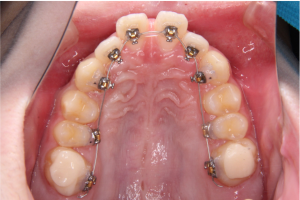

※矯正治療開始時の上顎咬合面

装置を上の歯の内側(口蓋側)に装着することで、正面から見た際に装置が目立ちにくい状態となります。